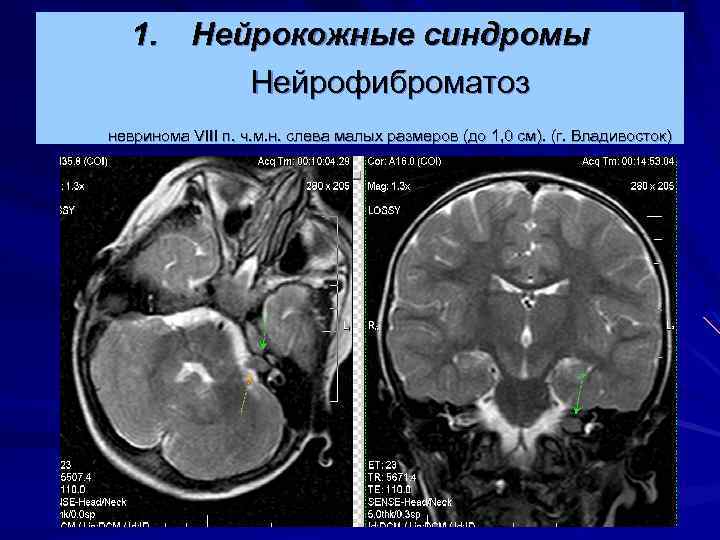

1. Нейрокожные синдромы Нейрофиброматоз невринома VIII п. ч. м. н. слева малых размеров (до 1, 0 см). (г. Владивосток)